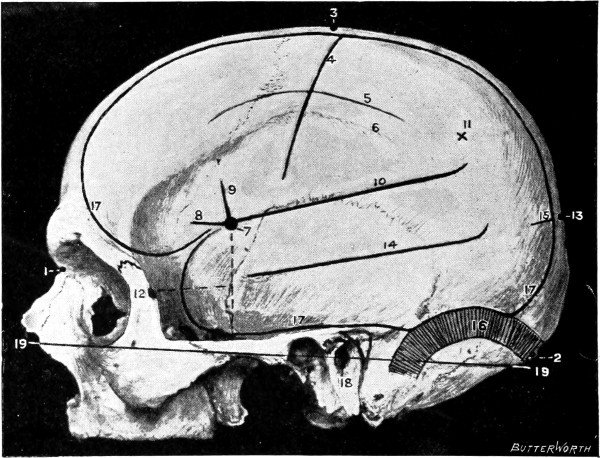

Fig. 1. Cranio-cerebral Topography. 1, The nasion; 2, The inion; 3, The mid-point between nasion and inion; 4, The Rolandic fissure; 5, The superior temporal crest; 6, The inferior temporal crest; 7, The Sylvian point; 8, The anterior horizontal limb of the Sylvian fissure; 9, The vertical limb of the Sylvian fissure; 10, The posterior horizontal limb of the Sylvian fissure; 11, The parietal prominence; 12, The malar tubercle; 13, The lambda; 14, The first temporo-sphenoidal sulcus; 15, The external parieto-occipital sulcus; 16, The lateral sinus; 17, 17, 17, The level of the base of the cerebrum; 18, The external auditory meatus; 19, 19, Reid’s base-line. (Reproduced, by the permission of Mr. H. K. Lewis, from the author’s work on ‘Landmarks and Surface-markings’.)